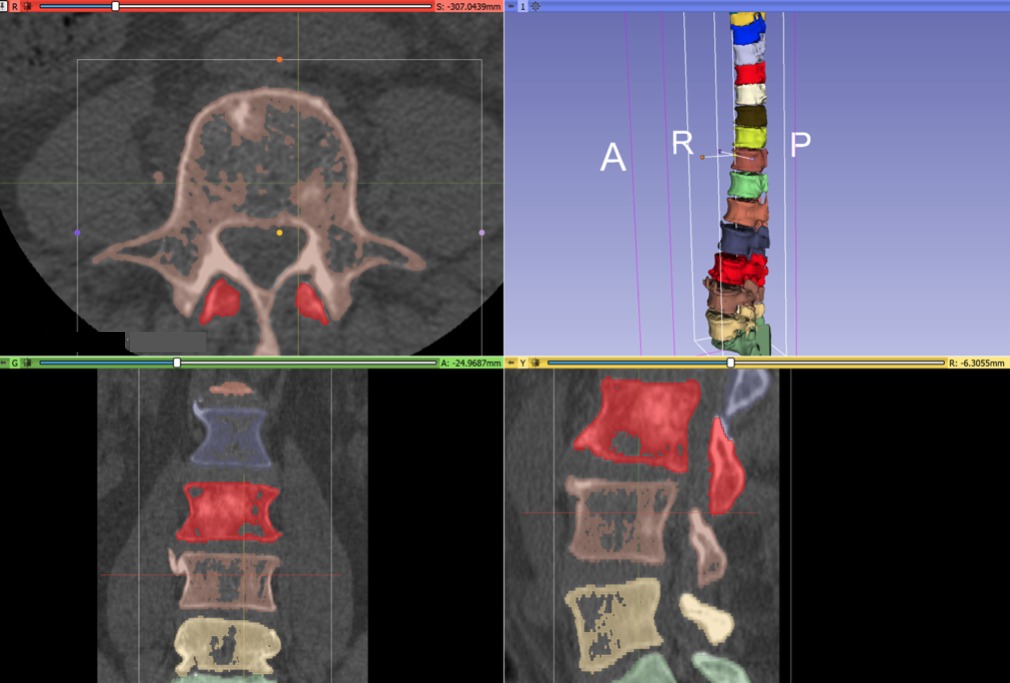

During the project week, we received consulting assistance on segmentation techniques from Andras Lasso and Rudolf Bumm. After Andras’ wrote us a post-processing script, the final result of registration is much better. These annotations can be used for neural net training:

Here is the MONAILabel server and Slicer Module running on Curt’s workstation. The app created annotations of vertebrae automatically created by a neural network trained using the VerSe spine dataset. This app works for interactively improving the segmentation through editing (using the deepedit algorithm):